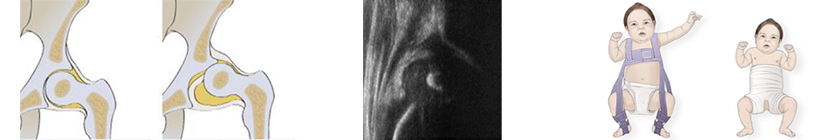

Displasia

Per displasia dell’anca si intende un’anomalia di sviluppo dell’articolazione per cui la testa femorale non viene più accolta perfettamente nella una cavità acetabolare. La familiarità rappresenta un’importante fattore di rischio.

Gli screening neonatali degli ultimi decenni hanno permesso di trattare con buoni risultati le anche displasiche dei neonati riducendo i danni tipici che si manifestano nell’età adulta.

Esistono diversi gradi di gravità della displasia: dalla lussazione alle alterazioni morfologiche minori che rappresentano una causa subdola di coxartrosi.